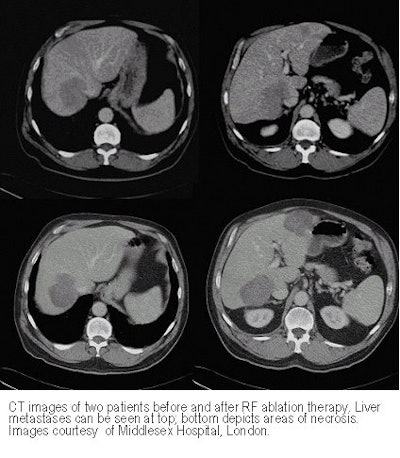

There were wide variations in outcomes as well, Gilliams said, showing CT images of two patients with metastatic liver disease. The first had large lesions that responded dramatically to chemotherapy. Two small remaining metastases were ablated with RF in January 1999, and the patient remained free of residual disease in May 2000.

But treatment was not always successful.

"This is the other side of the coin: a patient who at first scanned in October 1997 with lots of little areas of metastases, responding initially to chemotherapy, so that in May 1998 there was very little residual disease," Gillam said. "We treated her with radiofrequency , but as the chemo response faded, she developed multiple lesions, 10 or 12 more metastases [surrounding the area of necrosis]."